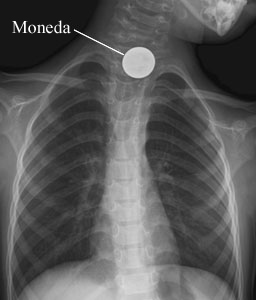

Radiografía de pecho de un objeto tragado